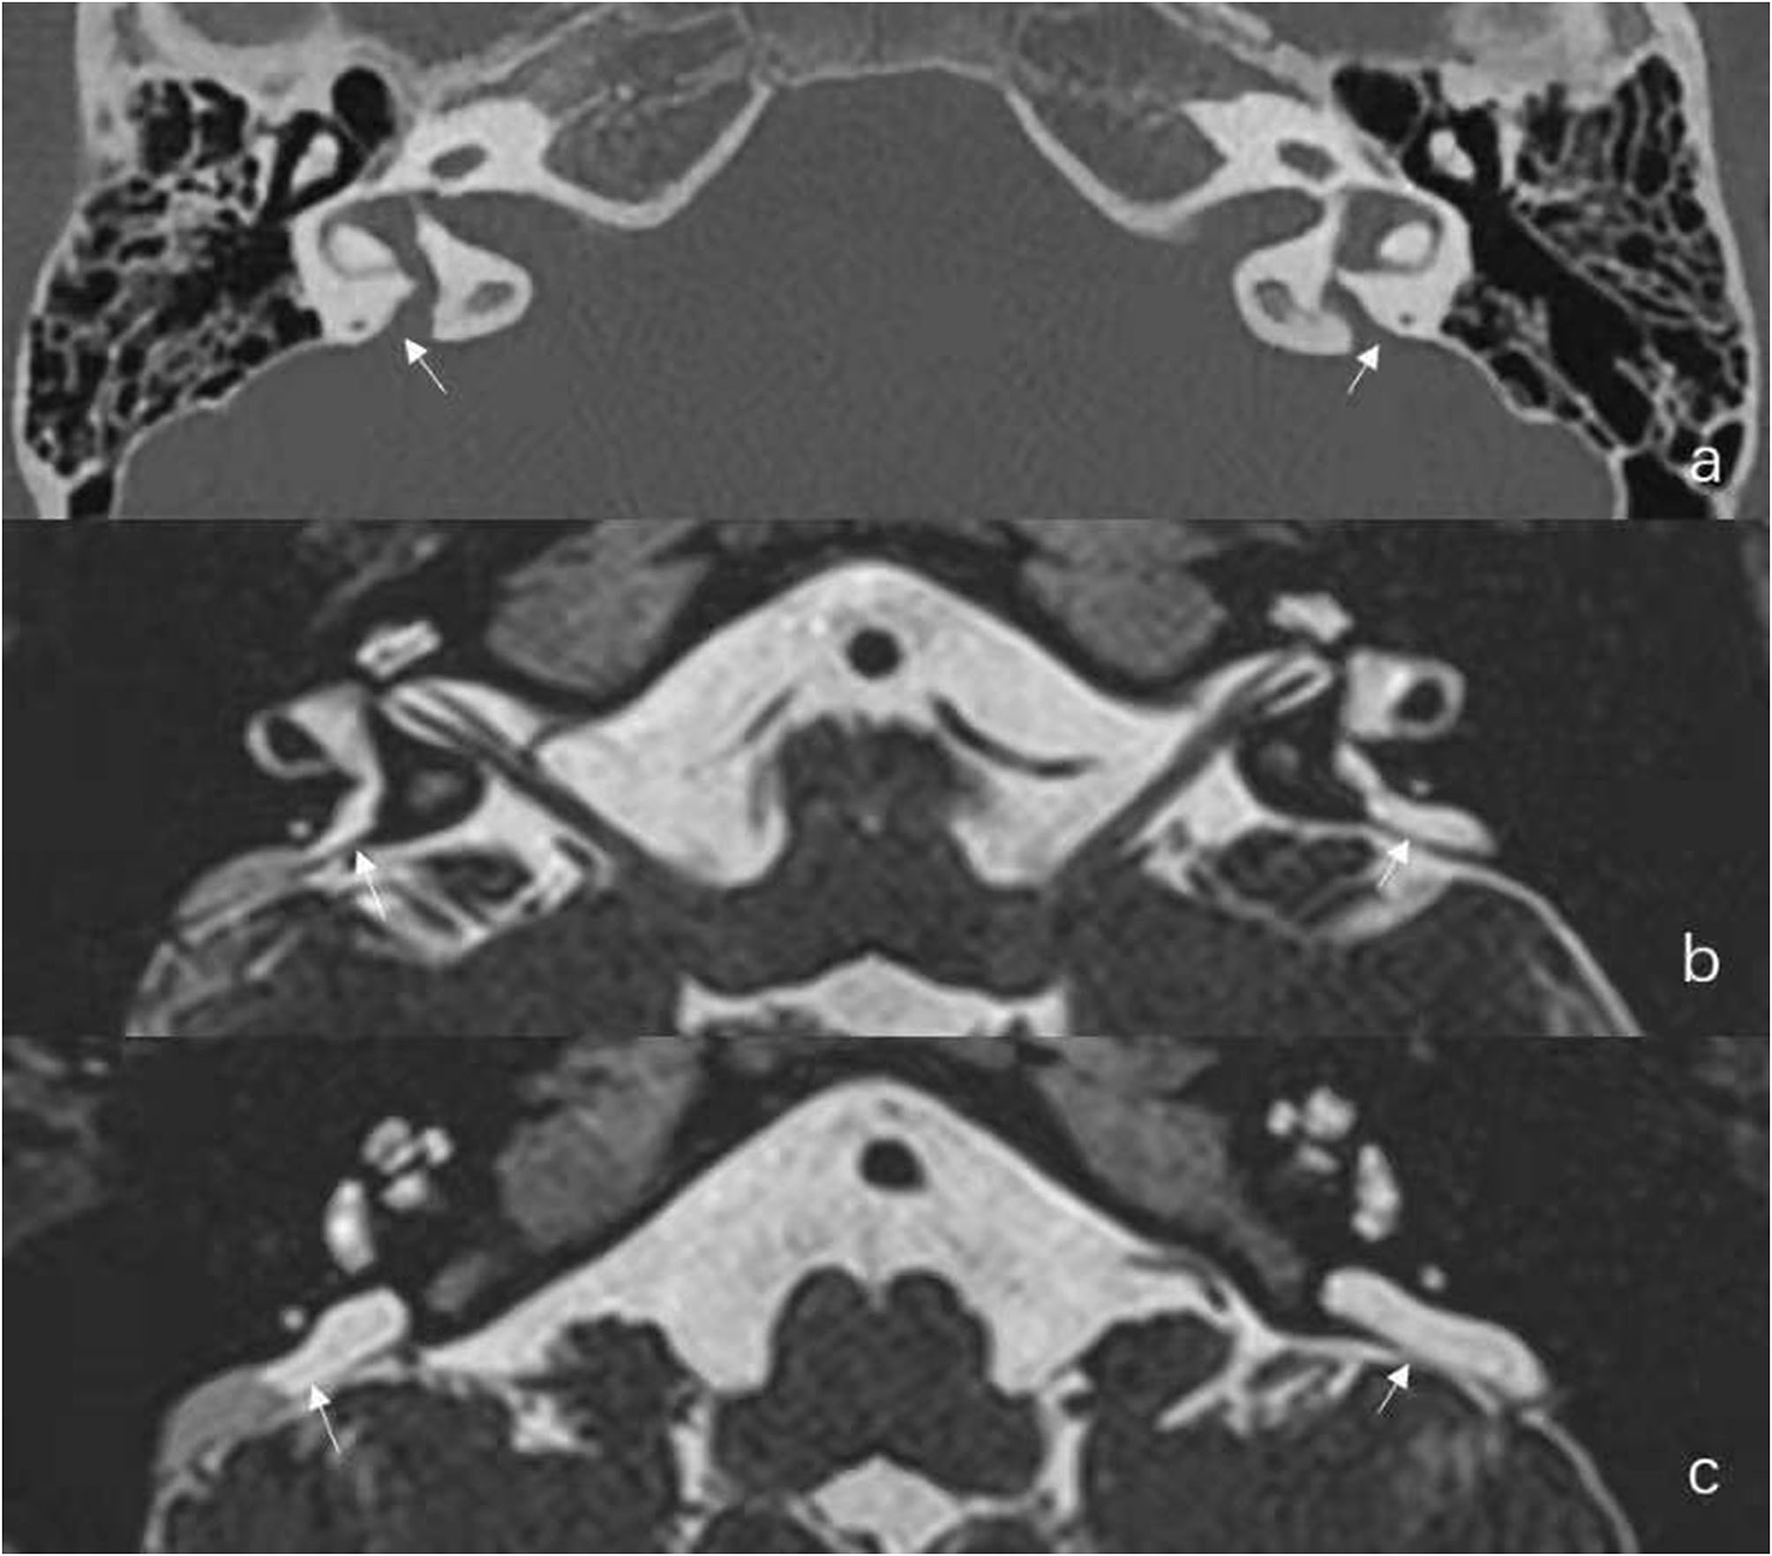

In this group, there were six females and three males, including five pediatric patients younger than 18 years old. The mean age was 16.9 years (range: 6–39 years). One case was diagnosed as unilateral EVA (case No. 1) and eight cases as bilateral EVA. Representative radiographic images are shown in Figure 1.

Figure 1

Radiological results of Case No. 2. (a) Axial temporal bone CT reveals the entire course of the large vestibular aqueduct extending from the crus communis of the vestibule to the posterior aspect of the petrous bone. (b,c) Additional axial Three-dimensional sampling perfection with application optimized contrasts using different flip angle evolutions (3D-SPACE) Magnetic Resonance Imaging (MRI) in the same child reveals enlarged endolymphatic duct (ED) and large endolymphatic sac (ES) containing variable signal intensity.